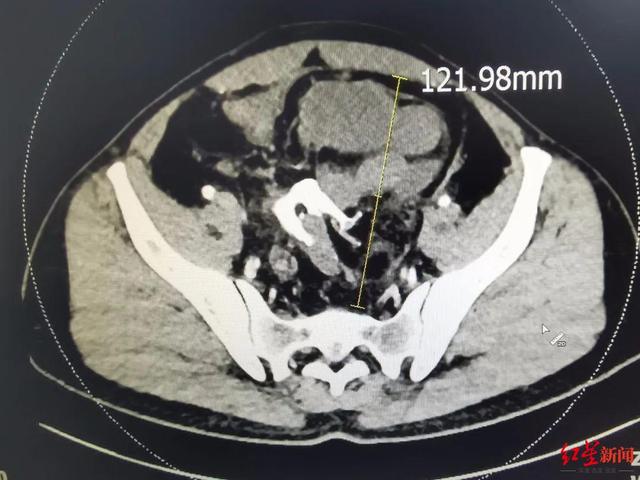

文章插图

畸胎瘤CT影像 。

比较大的畸胎瘤 , CT等检查甚至可以直接看到牙齿 。